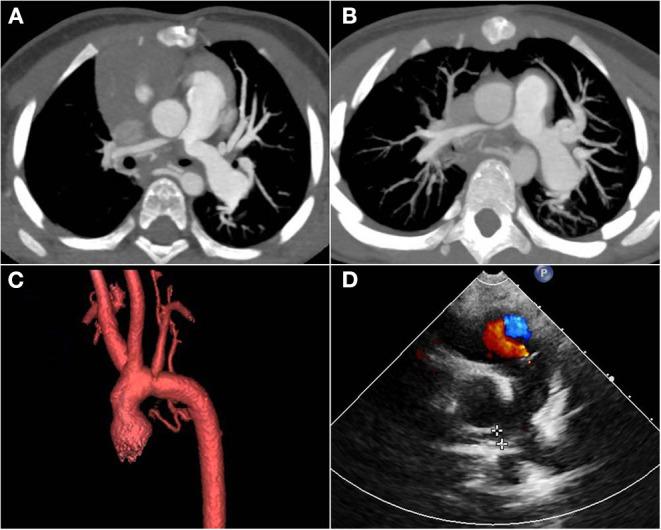

Berry syndrome is a challenging disease for surgeons to make early diagnosis and successful surgical correction in the neonatal period. Here, we summarized the clinical features of three neonates with berry syndrome in our center to optimize the therapeutic effect in the future.

From January 2014 to December 2019, three neonates with berry syndrome underwent one-stage surgical repair in our center. We mainly used two different surgical techniques to repair it, and collected clinical data retrospectively from hospitalization history, outpatient records, and telephone follow-up.

The age at operation was 28, 8, and 8 days and the body weight was 3.65, 3.86, and 3.0 kg, respectively. The morphology of the interrupted aortic arch (IAA) was type A in two patients and type B in one patient. The aortopulmonary window (APW) morphology was type IIa, III, and IIb, respectively. The phenotype of the IAA type B combined with APW type III in our second patient was reported for the first time so far. All patients survived and were followed up to date. The second patient using intra-aortic baffle experienced twice reoperation for right pulmonary artery (RPA) stenosis. All patients grew well so far.

手术年龄分别为28天、8天和8天,体重分别为3.65kg、3.86kg和3.0kg。2例患者中断性主动脉弓(IAA)形态为A型,1例为B型。主肺动脉窗(APW)形态分别为IIa型、III型和IIb型。迄今为止,首次报道了我们第二例患者中IAA B型合并APW III型的表型。所有患者均存活并随访至今。第二例使用主动脉内挡板的患者因右肺动脉(RPA)狭窄接受了两次再次手术。到目前为止,所有患者生长良好。